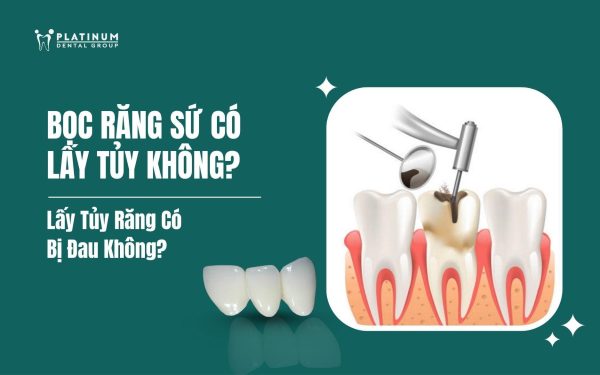

Làm sao để răng trắng sáng hơn? Dán sứ Veneer khác gì bọc răng sứ? Phương pháp nào phù hợp với bạn? Tại chuyên mục này, các bác sĩ Platinum Dental sẽ giải đáp rõ ràng, dễ hiểu mọi thắc mắc về cải thiện nụ cười, giúp bạn tự tin lựa chọn giải pháp thẩm mỹ tối ưu và phù hợp nhất với bản thân!!